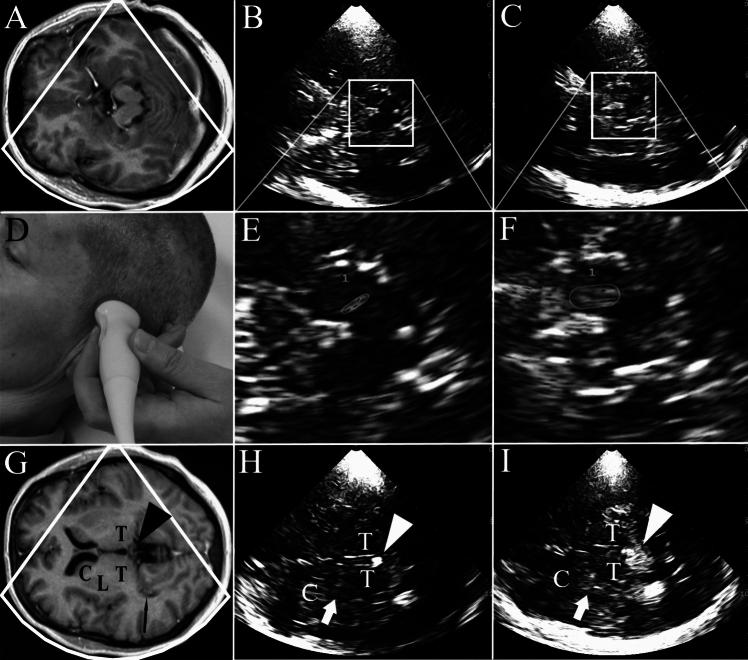

Transcranial brain parenchyma sonography (TCS) has been recommended as a tool for the early and differential diagnosis of Parkinson's disease (PD) in German and European clinical guidelines. Still, the brain structures to be examined for the diagnostic questions and the requirements for being a qualified investigator were not specified in detail. These issues have now been addressed in the 2023 update of the clinical guideline on PD by the German Society of Neurology (DGN).

Three diagnostic questions were defined: (1) What is the accuracy of TCS in the differential diagnosis of PD versus atypical and secondary Parkinsonian syndromes? (2) What is the accuracy of TCS in the differential diagnosis of PD versus essential tremor? (3) What is the accuracy of TCS in the diagnosis of PD in persons with typical early symptoms, compared with the diagnosis established by clinical follow-up? The brain structures to be assessed and the level of recommendation were formulated for these questions. The training requirements for being regarded as qualified TCS investigator were stipulated by the responsible medical societies (German Society of Ultrasound in Medicine, DEGUM; German Society for Clinical Neurophysiology and Functional Imaging, DGKN). Finally, the recommendations for these diagnostic questions reached strong consensus (each ≥ 97%) of the guideline committee. Here, the details of review and recommendations are presented.

The updated guideline clarifies the diagnostic uses and limitations of TCS in PD.